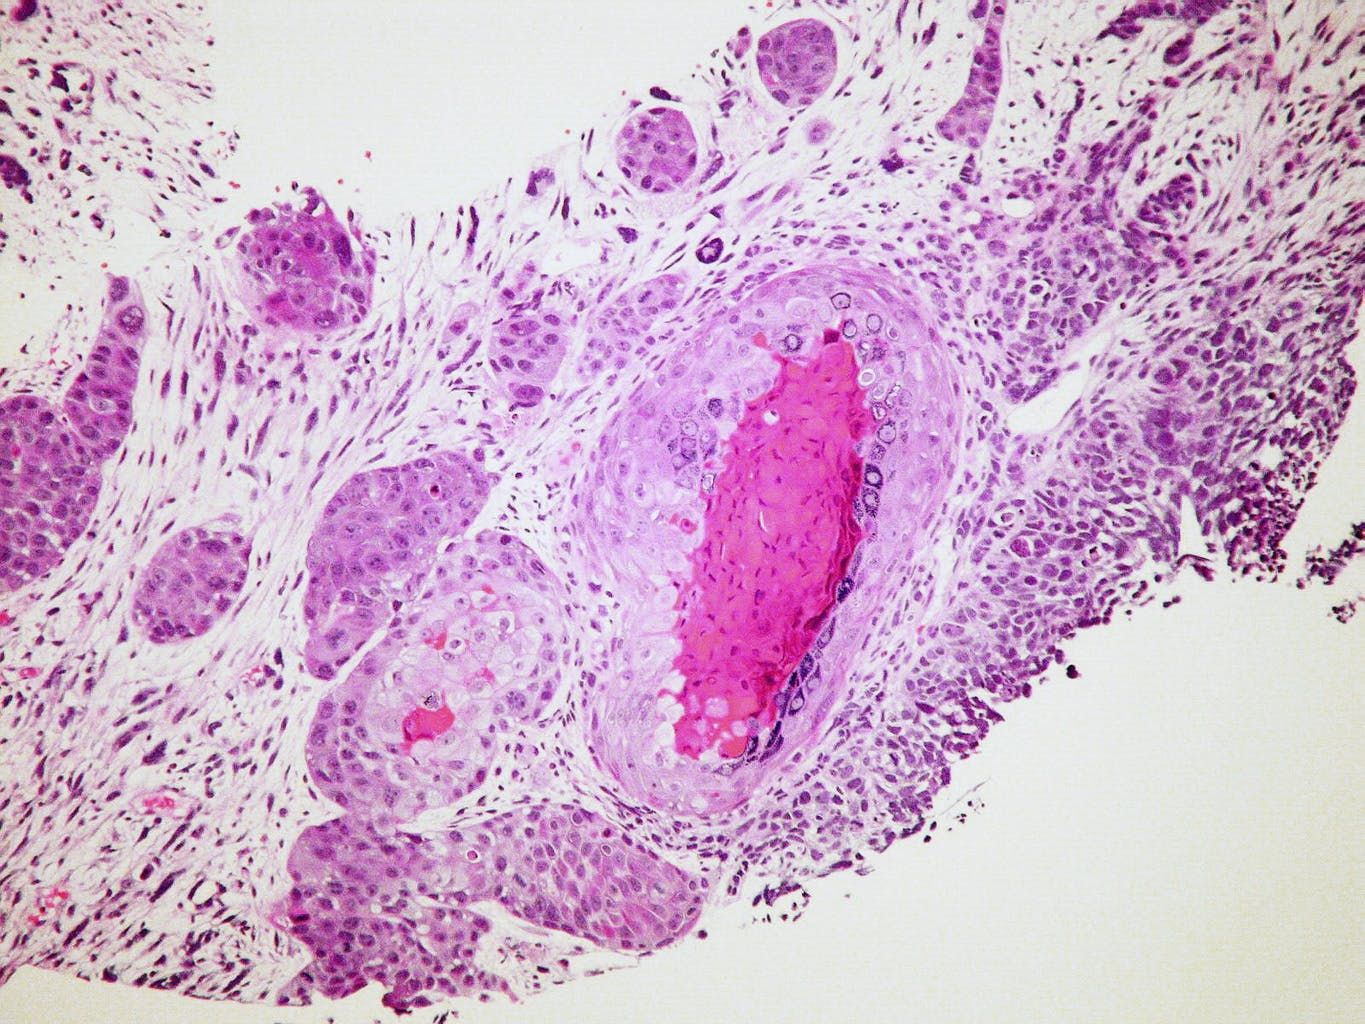

According to the NCI data, cannabis has been shown to critically damage

or kill cancer cells in cases of liver cancer and additional varieties

of the disease. When the effects of medical cannabis on cancer were

as well as breast cancer cells. In the breast cancer study, researchers

found that, while the medical cannabis killed the cancer cells, it did

not negatively affect healthy breast cells.

Additionally, when the effects of medical cannabis were studied on

metastatic breast cancer, the treatment was shown to lessen the number,

size and spread rate of tumors in the body.